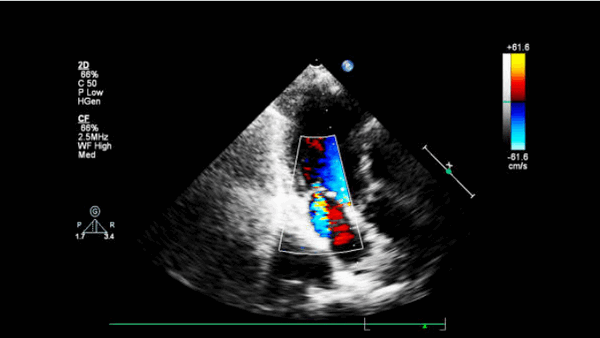

С помощью допплеровского картирования можно выявить скорость и направление потоков крови в полостях сердца, что позволяет определить клапанную недостаточность или стенозы, дефекты межпредсердной и межжелудочковой перегородок.

Эхокардиограмма может не только создавать ультразвуковые изображения структур сердца, но и производить точную оценку кровотока через сердце с помощью Допплеровской эхокардиографии с использованием импульсного или непрерывного Допплеровского ультразвука. Это позволяет оценить как нормальный, так и аномальный кровоток через сердце. Цветной Допплер, как и спектральный Допплер, используется для визуализации любых аномальных связей между левой и правой сторонами сердца, любой утечки крови через клапаны (клапанная регургитация) и оценки того, насколько хорошо клапаны открываются (или не открываются в случае клапанного стеноза). Метод можно также использовать для движения ткани и измерения скорости движения стенок сердца.

- Острый дефект межжелудочковой перегородки (ДМЖП). Эта патология часто происходит около верхушки сердца и чаще встречается при нижнем инфаркте левого и инфаркте правого желудочков. Нарушение непрерывности МЖП можно увидеть на 2-D эхокардиограмме в апикальной 4-камерной, парастернальной длинной оси и короткой оси. Цветное допплеровское картирование может точно показать дефект. Импульсно-волновой допплер, перемещенный вдоль правой стороны МЖП (парастернальная длинная ось или иногда четырехкамерная проекция), может показать турбулентную струю сброса.

- Чувствительность цветового допплера при эхокардиографии для обнаружения ДМЖП находится в диапазоне> 95%. Ширина цветной допплеровской струи коррелирует с размером дефекта при операции или патологии.